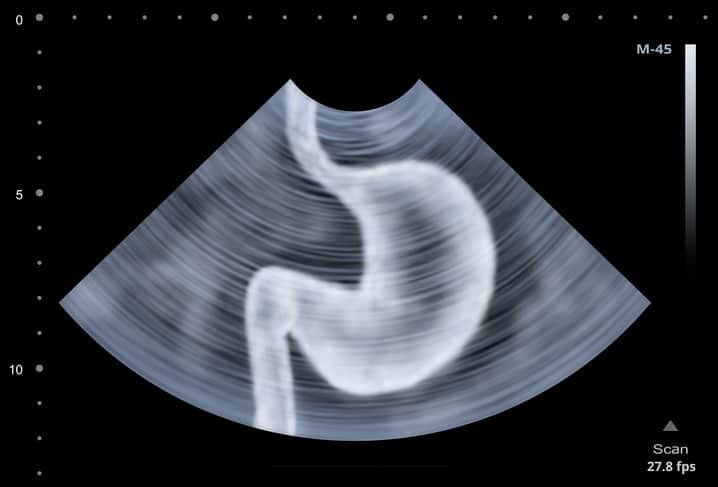

Gastroesophageal reflux disease (GERD) adalah penyakit pada sistem pencernaan yang ditandai dengan naiknya asam lambung naik menuju kerongkongan.

Jika tidak ditangani, asam lambung yang naik dapat menyebabkan iritasi pada lapisan dalam kerongkongan.

Gejala umum GERD meliputi rasa terbakar pada dada (heartburn) terutama pada malam hari atau setelah makan.

Faktor-faktor yang meningkatkan risiko timbulnya GERD yakni obesitas, kehamilan, hernia, dan terhambatnya pengosongan lambung.

Gangguan pencernaan ini juga bisa dipicu oleh kebiasaan merokok, makan dalam porsi besar, dan konsumsi aspirin.